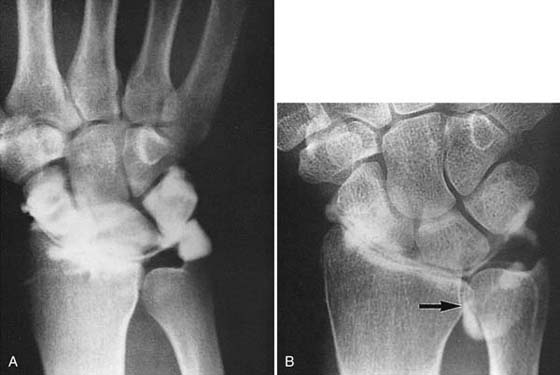

Figure 13-10 Thumb dislocation. A, This patient’s left thumb appears normal under radial stress. B, The right thumb, which had a disruption of the ulnar collateral ligament, shows subluxation of the first metacarpophalangeal joint when subjected to the same stress.

images

Figure 13-11 When this patient clenched the fist in supination, subluxation of the scaphoid (arrow) occurred.

Figure 13-12 Fracture of the trapezial ridge. A, This routine posteroanterior view of the wrist is normal. B, A supinated oblique view shows a fracture of the trapezial ridge (arrow). C, A carpal tunnel view in the same patient also demonstrates this type of fracture (arrow).

Figure 13-13 Carpal tunnel view showing a fracture of the hook of the hamate (arrow).